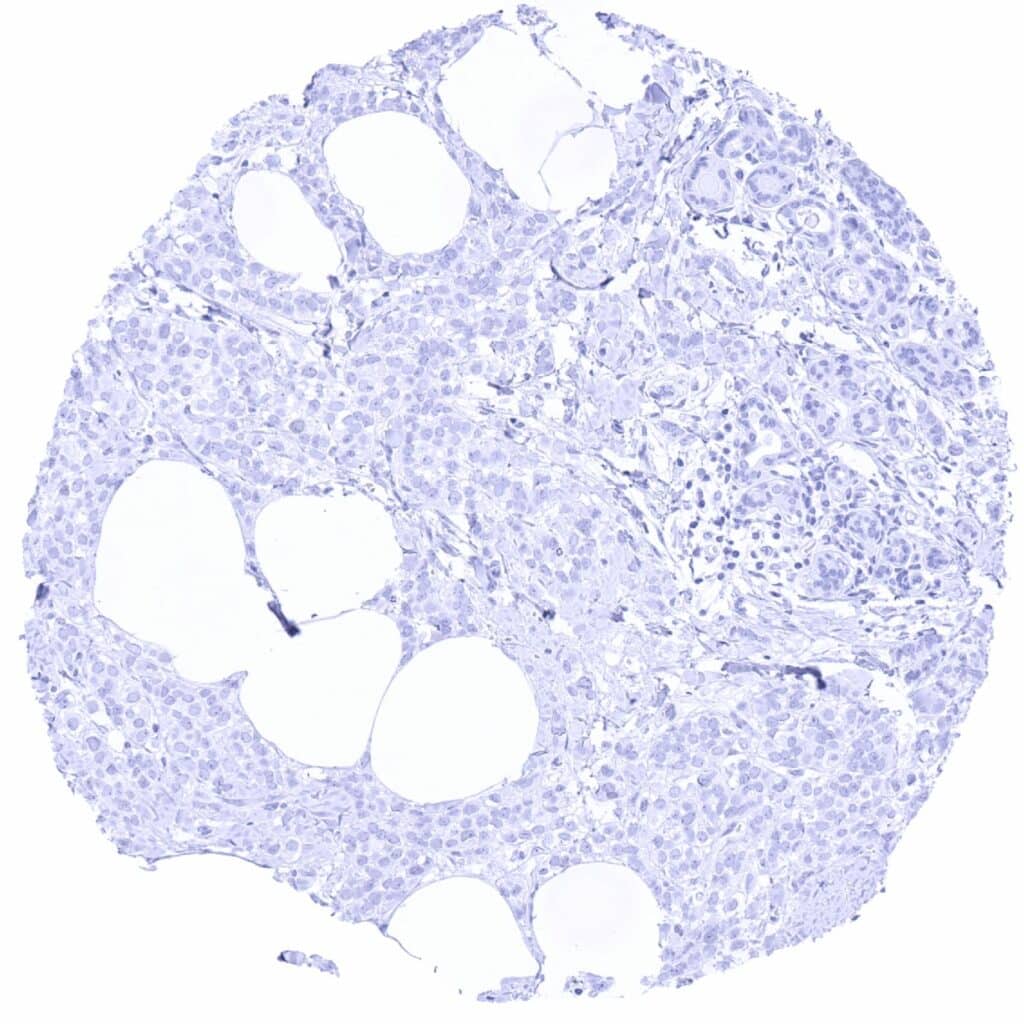

Pancreas PAX6 negative neuroendocrine tumor